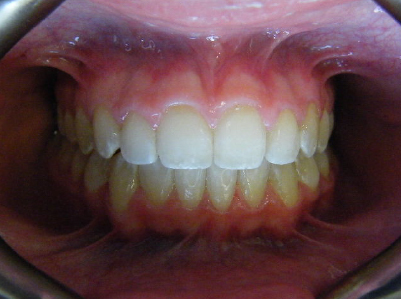

Patient 2: Significant increased overjet and upper and lower crowding.